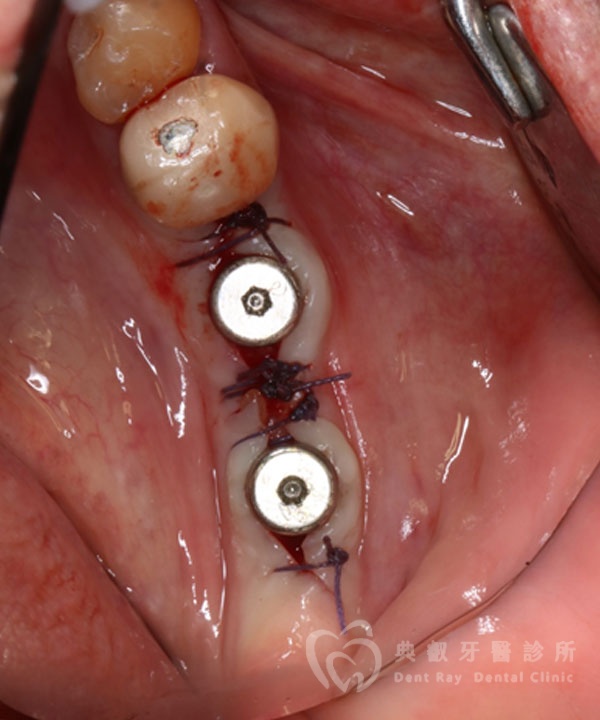

植牙案例三